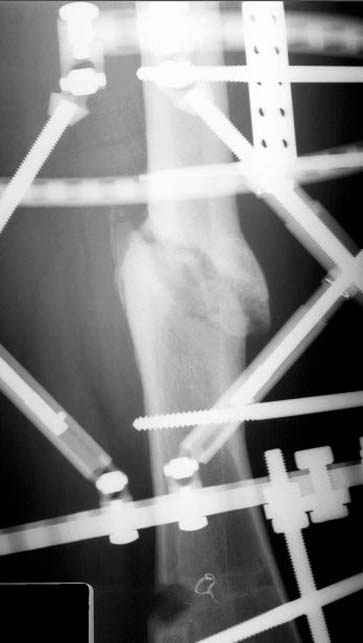

Несколько снимков из моей коллекции, чтобы разьяснить, почему мы до сих пор делаем различные варианты остеотомии.

На рисунке N1 предоперационный план лечения ложного сустава шейки бедра- линия ложного сустава, угол и направление введения импланта, клиновидная остеотомия в градусах и миллиметрах, второй снимок после коррекции, расчет, на сколько удлиняется конечность и размеры импланта;

N3 рисунок окончательный снимок, после операции моя рентгенограмма должен выглядеть примерно как эта картина. На N4 снимке клин перед удалением; N5 послеоперации 3 нед.; N6 окончательная рентгенограмма.

Отправитель: Djoldas Kuldjanov 23 Ноябрь 2004, 18:21

пластическая модель; и коррекция бедра аппаратом Илизарова.

Имею другие снимки тоже, получится как отчет о моей работе.